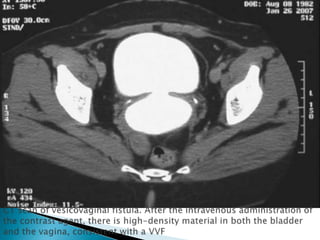

 Modern imaging technique contarst CT and MRI have

limited value.